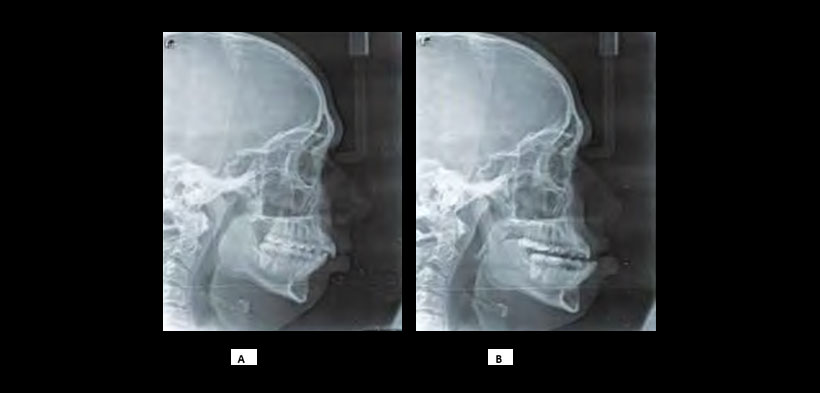

Fig. 3. Radiografía lateral de control, en A) se muestra el calibre de la vía aérea disminuida ligeramente. En la imagen B) se muestra la radiografía control luego de la colocación del dispositivo de avance mandibular, nótese el aumento del calibre de la vía aérea.